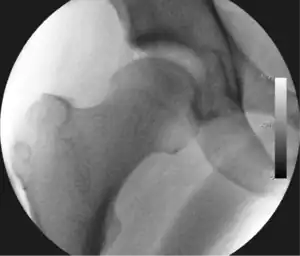

![]() Intraoperative fluoroscopic image during an arthroscopic resection of a cam lesion of the femur. The upper instrument is the arthroscope (viewing device), while the lower is the high-speed burr used for reshaping the bone. |

Standard arthroscopic treatment of symptomatic cam FAI involves debridement (resection) or repair of any labral [10] and chondral injuries [11] in the central compartment of the hip, and subsequent reshaping of the head-neck junction of the upper femur (osteochondroplasty) in the peripheral compartment [12][13] using high-speed motorised burrs that are similar in design to a dentist's drill (see fig. 9).